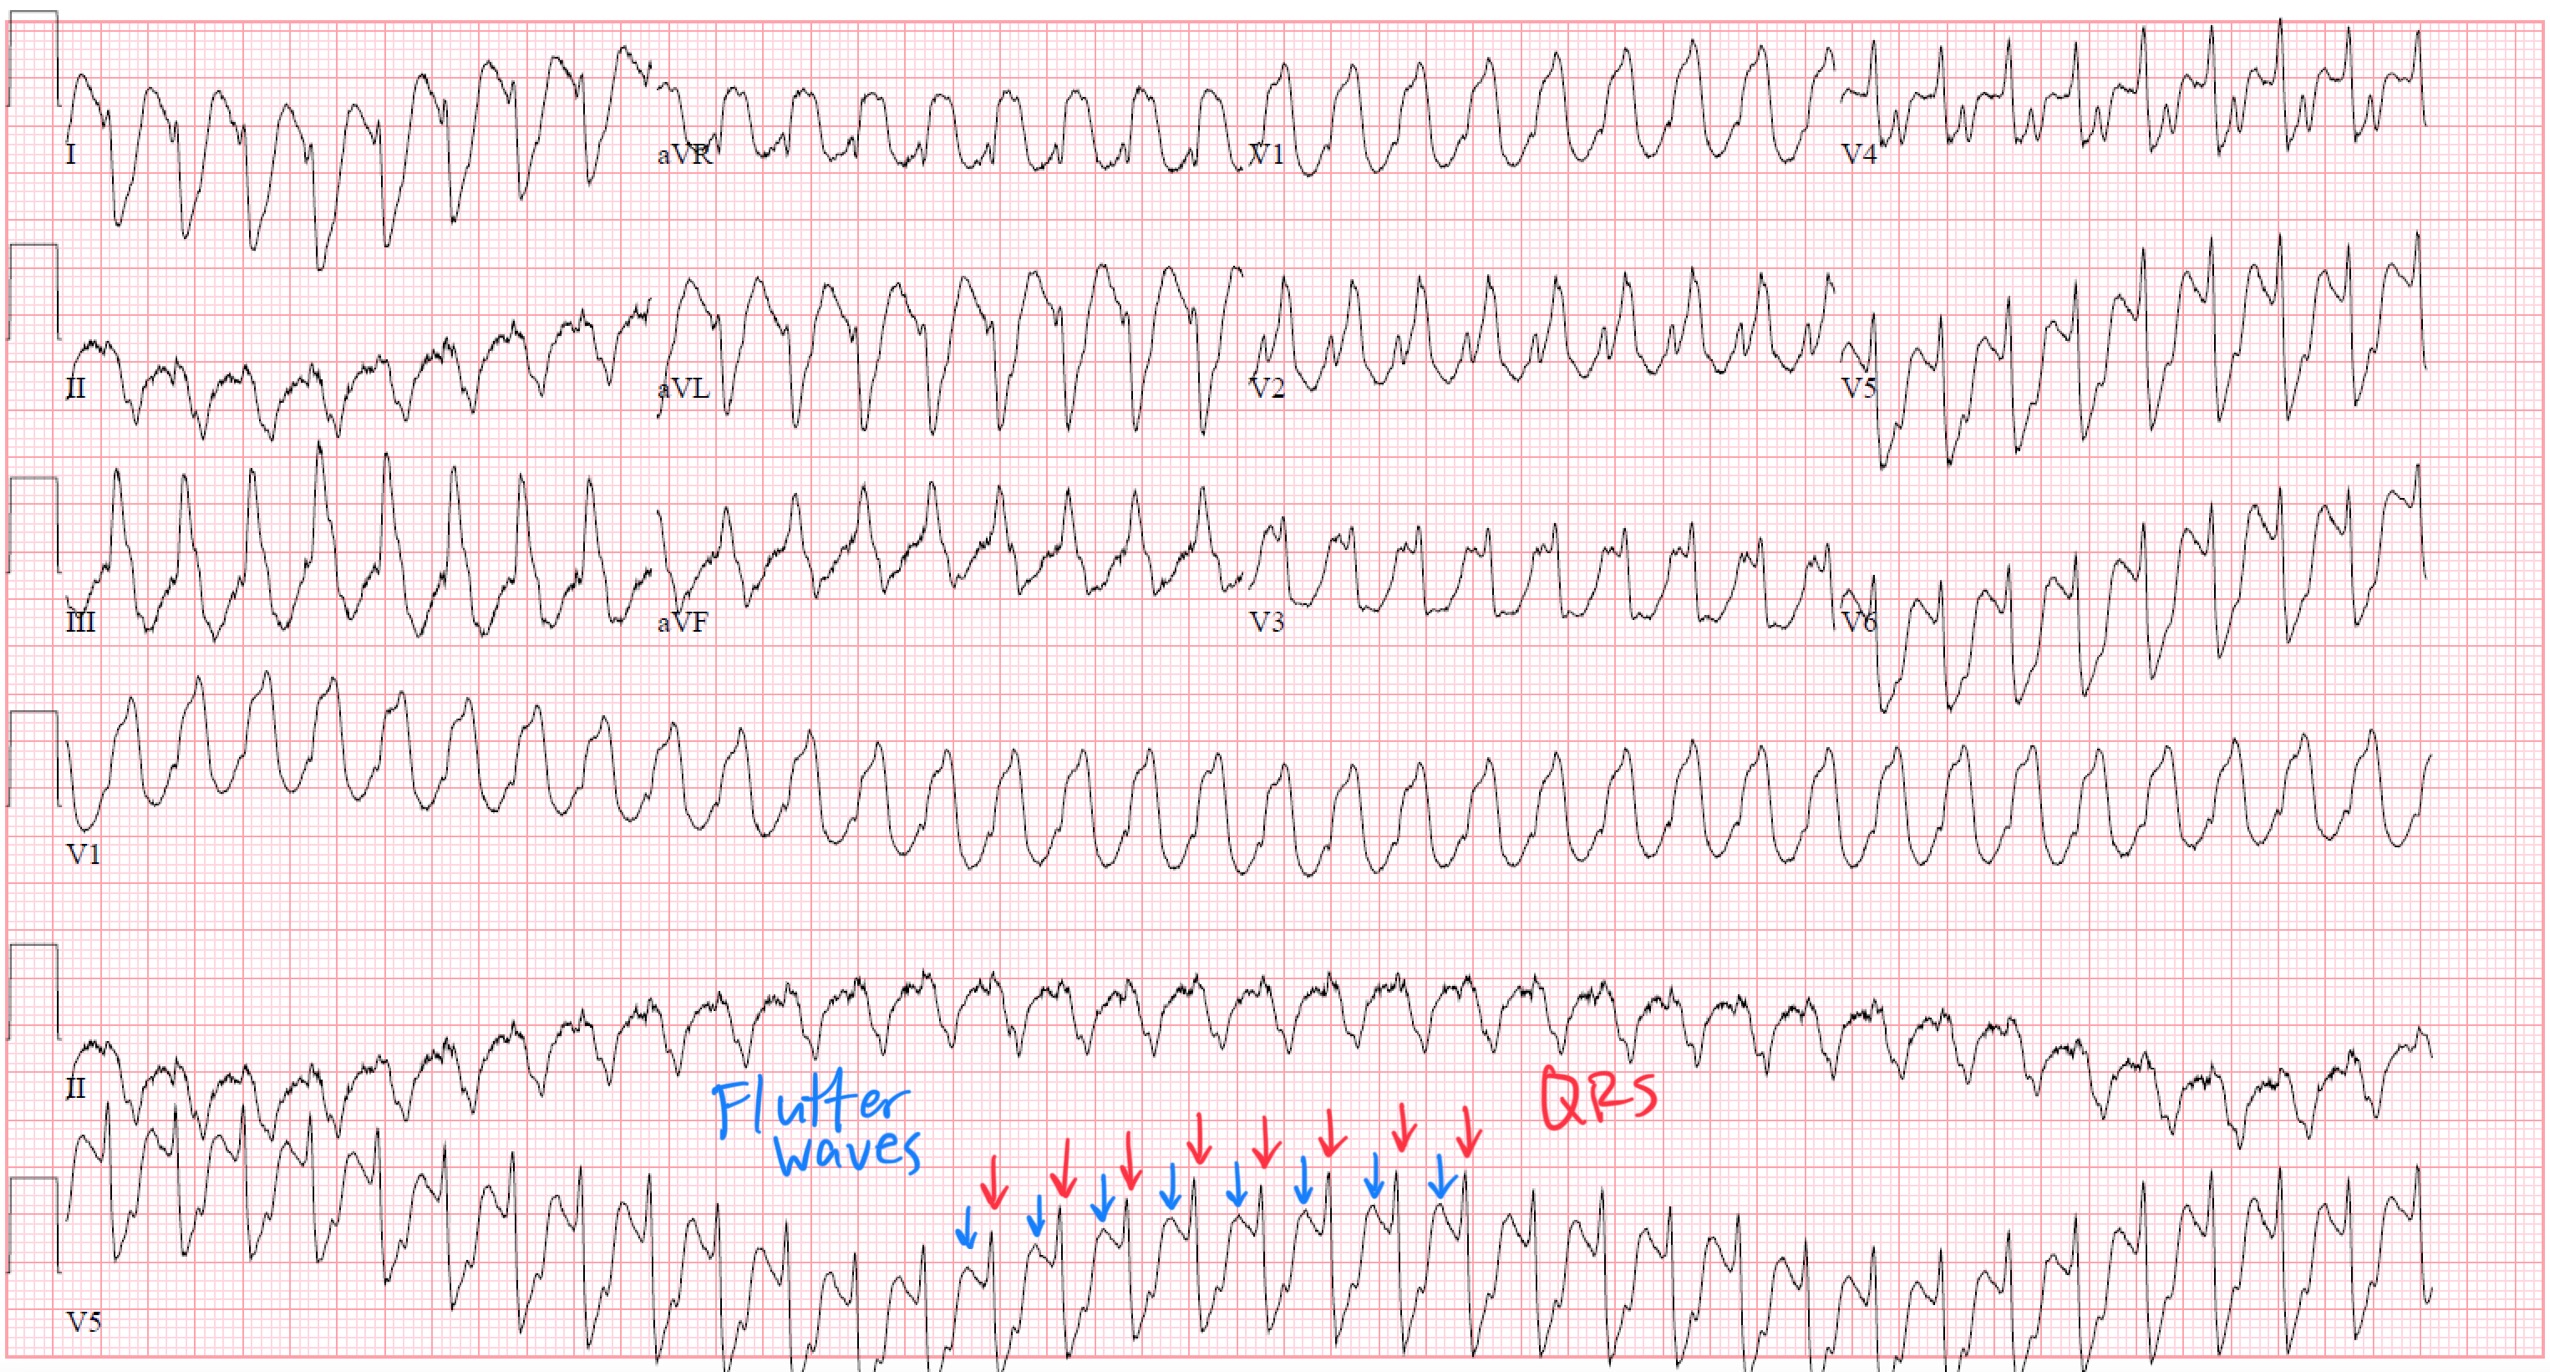

ECG Findings

Key ECG clue:

If a “regular wide-complex tachycardia” has a ventricular rate near 250 bpm in a patient on flecainide, suspect 1:1 atrial flutter.

Look carefully in V1 or inferior leads — you may find subtle flutter waves embedded within the T waves or ST segment.